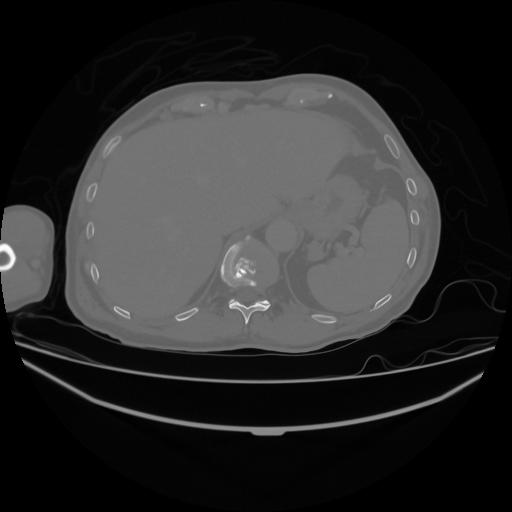

5 CUERPO,CE,Vol,1.0,CUERPO,,